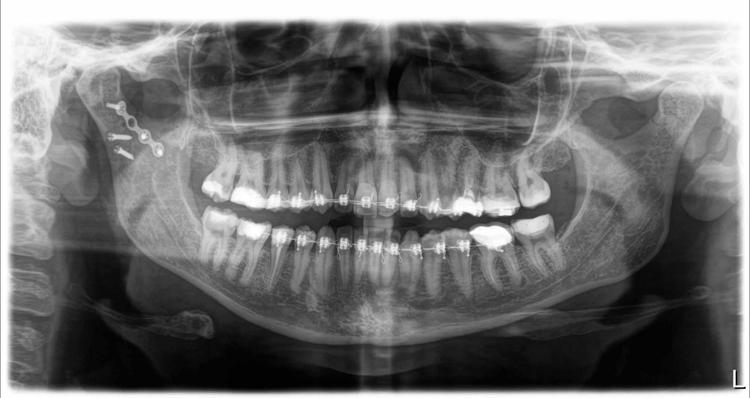

Tekerlek o mazgala girdi. Öne doğru savruldum ve çenemi çarptım. Çenem, burnum, bütün yüzümü yere çarptım. Olayın sıcağıyla başta anlamadım. Çene kemiğim iki taraftan kırılmış. Çok büyük bir cerrahi ameliyat geçirdim. Ameliyat öncesinde dişlerime tel takıldı.

10

Çünkü lastikle çenemi oturtmaları gerekiyordu. Ameliyatın yapıldığı yerden yüz sinirleri geçtiği için, sağ tarafımda yüz sinirlerimde geçici yüz felci oluştu. Gözüm kapanmıyordu, güldüğüm zaman ağzım hareket etmiyordu. Çiğneme, yemek yiyememe bir tarafa, ağrılarım dayanılmazdı. 6-7 ayı buldu iyileşmem. Sağ tarafım, ameliyat sonrası başka bir ben oldu. Bu olaydan sonra uygulamayı hemen sildim ve çevremdeki insanlara da başıma geleni anlatıp kullanmamalarını öneriyorum."